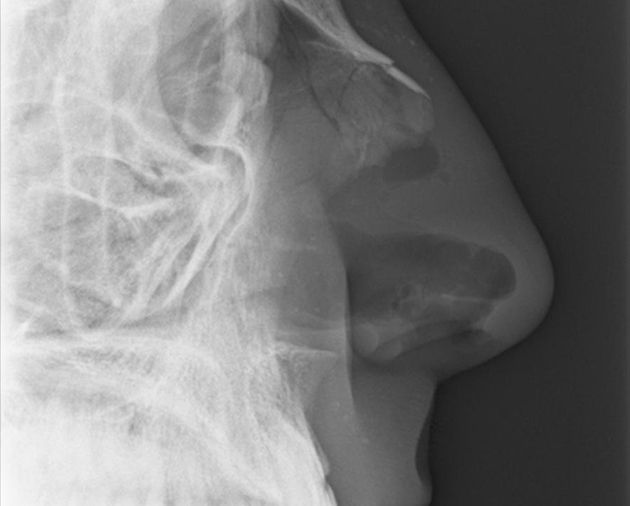

X-ray image courtesy of Willy Nast

They called my name and led me to an examination room. The doctor looked up my nostrils and slid a long cotton swab deep into each cavity to clear the dried blood. My eyes watered. She asked me if my nose had always been curved. She ordered an X-ray.

I followed Jamie, the X-ray technician, to the cool metal room where he would take the images of my face. He carried a springy energy in his legs that that felt somehow familiar. When we reached the X-ray table, he turned and studied my face.

“Left hook?” Jamie asked. Then he took a half-step backward, pointing his shoulder toward me, bent his knees and rocked gently on the balls of his feet—the boxing stance. The very first thing they teach you at a boxing gym.

“I see it,” he said, smiling and cocking his right fist. “It had to be a right hand.” He sat me in a chair next to the table.

“No,” he answered, positioning my head sideways on the X-ray table, as if I were taking a nap in the middle of dinner. “I took a lot of martial arts when I was younger. My brother was a boxer, though.” He aligned the X-ray tube over my head, and stepped behind the protective wall to take the pictures.

It’s not that I fear another injury; that fear has always been there. It’s not the memory of the moment of impact and the crunching sound I heard in my head. It’s not the way the blood tasted in my mouth or the look of the crooked line in Bill’s nose. What haunts me is the way Jamie slid the negative over the soft backlight, and tapped the black and gray image of my skull with his forefinger.

“You had to know,” he said. “Something like this was bound to happen.”